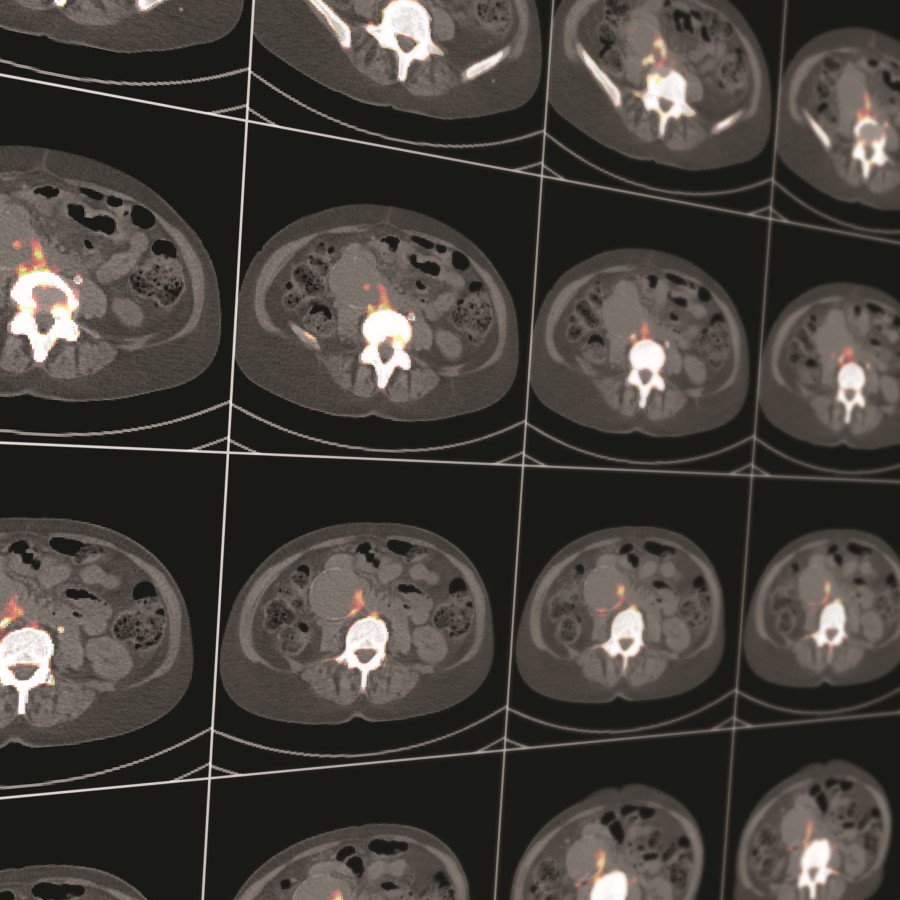

MRI is crucial because it provides high-resolution images of the heart's structure. Dr Banerjee’s MultiMeDIA lab specialises in multimodal medical data integration, and was therefore perfectly poised to develop a new computer tool that creates detailed 3D reconstructions of the heart's left atria from MRI scans. These reconstructions were then integrated with charge density mapping, which shows the patterns of electrical conduction during AF. This combination provides doctors with both structural information from MRI and detailed electrical patterns from charge density mapping - essentially creating a more complete picture of what may be causing AF in a patient.

Hero image caption: Integration of Magnetic Resonance Imaging (MRI) with electrical mapping data from charge density mapping can offer new insights into the treatment of atrial fibrillation. This approach allows for a more comprehensive understanding of the structural and electrical characteristics of the heart's atria, which are crucial in planning and improving treatment strategies for this common cardiac arrhythmia.